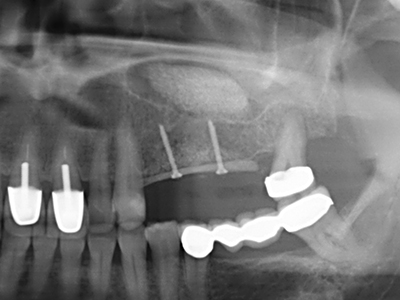

Indication: Sinus lift

Preparation of the lateral window during an external sinus floor elevation is challenging, particularly for implantologists with little surgical experience. Removal of the bone cover of the sinus without injuring the underlying Schneiderian membrane is only part of the operation – after establishing an adequate access, the membranous lining of the sinus must be carefully mobilized to make space for the augmentation materials or the implants. Piezo surgery is useful for this indication in two ways: diamond-coated instruments can be used for selective bone ablation and the underlying mucous membrane remains intact when the procedure is done carefully. The ultrasonic frequencies also enable detachment of the mucous membrane without complications – the frequencies are transmitted into the space between the mucous membrane and sinus floor by special blunt attachments (Cassetta, Ricci et al. 2012, Pereira, Gealh et al. 2014) (Rickert, Vissink et al. 2013). As a result, it is not surprising that current reviews of external sinus floor elevation positively evaluate the use of piezoelectric devices as well as the use of roughened implant surfaces and bone replacement materials (Wallace, Tarnow et al. 2012).

As shown in the past, basically any bone surgery procedure represents a possible indication for piezo surgery. Thus preparation of the mobile segment in distraction osteogenesis (Fig. 23-25) and sandwich osteotomy uses special attachments without endangering the blood supply to the crestal section, which is essential for the success of both techniques (Gonzalez-Garcia, Diniz-Freitas et al. 2008).

For removal of an implant, a vestibular bone cover that is replaced after removal of the implant screw can be prepared to retain the contour of the alveolar ridge.

There are additional applications in sinus surgery. Pathologies and foreign bodies can be removed from the sinus after concentric preparation of a generally trapezoid bone cover in the facial sinus wall. The bone cover is repositioned on conclusion of the intra-antral operation component and secured by wedging or adaptive sutures to prevent dislocation.

Purely orthodontic indications include orthognathic surgery, genioplasty (Fig. 27-30) and orbital decompression in patients with advanced endocrine orbitopathy as a result of Basedow’s disease (Ponto, Zwiener et al. 2014). Piezo devices are also used in maxillofacial surgery and to remove tumours at the base of the skull in various hospitals.